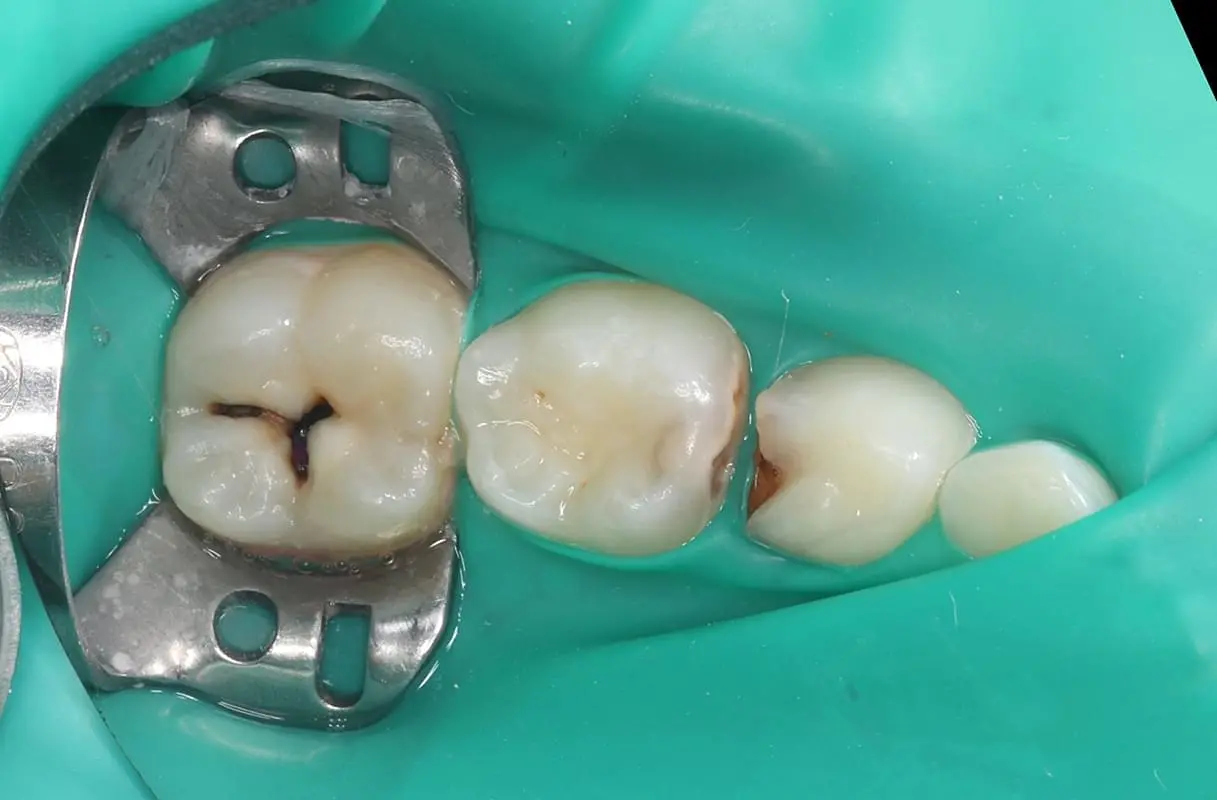

В нашому курсі ми зробили акценти саме на лікуванні карієсу у дітей, зосередились на особливостях карієсології саме у дітей. Ми висвітлюємо і детально розбираємо ці особливості, починаючи від класифікації, особливостей препарування та підбору реставраційних матеріалів, технік відновлення твердих тканин і до мінімально інвазивних методик в дитячій стомтаології. На відеодемонстраціях ми детально демонструємо етапи і послідовність відновлення уражених твердих тканин різних груп зубів у дітей, що допоможе максимально освоїти тематику карієсології та робить курс максимально практичним.

• Модуль 8. Техніки відновлення твердих тканин тимчасових і постійних зубів у дітей.

• Модуль 9. Мінімально інвазивні методики лікування карієсу у дітей.

• Модуль 10. Відеодемонстрація відновлення дефекту 1 класу за Блеком тимчасових молярів композиційним матеріалом на фантомі.

• Модуль 11. Відеодемонстрація відновлення дефекту 2 класу за Блеком тимчасових молярів композиційним матеріалом на фантомі.

• Модуль 14. Клінічна відеодемонстрація відновлення дефекту 1 класу за Блеком тимчасових молярів композиційним матеріалом.

• Модуль 15. Клінічна відеодемонстрація відновлення дефекту 2 класу за Блеком тимчасових молярів композиційним матеріалом.

• Модуль 16. Клінічна відеодемонстрація дефектів тимчасових різців композиційним матеріалом.

• Модуль 17. Клінічна відеодемонстрація відновлення жувальної поверхні постійного шостого зуба.